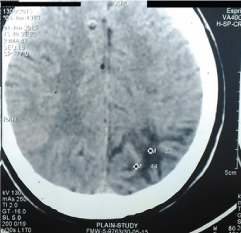

Electroencephalogram (EEG) was normal. CT scan of the brain was suggestive of hypodense lesion in left posterior parietal lobe [Table/Fig-1] with dilatation of ipsilateral occipital horn of left lateral ventricle [Table/Fig-2], but inconclusive. MRI showed T1 hypo intense [Table/Fig-3], T2 [Table/Fig-4] and Fluid Attenuation Inversion Recovery (FLAIR) hyperintense signal in left posterior parietal region with focal irregularity of gyral pattern and dilatation of occipital horn. There was no restriction of diffusion noted in lesion in Diffusion Weighted Imaging (DWI). Apparent Diffusion Coefficient (ADC) exhibited hyper intense signal in the lesion. There were no abnormal flow voids. The lesion was non-enhancing and perifocal irregular nodular foci of enhancement were noted in post-contrast study with no perifocal oedema or mass effect [Table/Fig-5]. These features were suggestive of a porencephalic cyst along the superior convexity of left posterior parietal lobe with gliosis. The differential diagnoses include cystic lesions such as arachnoid cyst, epidermoid cyst.

Non-contrast computed tomography brain showing hypodense lesion in left posterior parietal lobe.

With dilatation of ipsilateral occipital horn of left lateral ventricle.